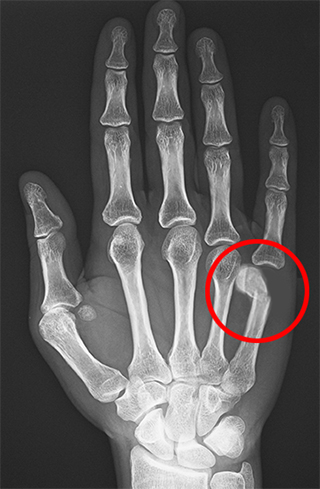

A boxer’s fracture is a break in the neck of the fifth metacarpal bone of the hand (below the pinky finger) close to the knuckle. The hand is composed of 3 types of bones: carpal or wrist bones, metacarpals or long hand bones, and phalanges or finger bones. Metacarpals consist of five long bones that connect the carpal with the phalanges. Structurally, metacarpal bones can be divided into four parts: base, shaft, neck, and head. In some cases, the broken bone can protrude through the skin and is called an open fracture.

- Imaging studies such as X-ray, MRI or CT-scan will be ordered to confirm the diagnosis.